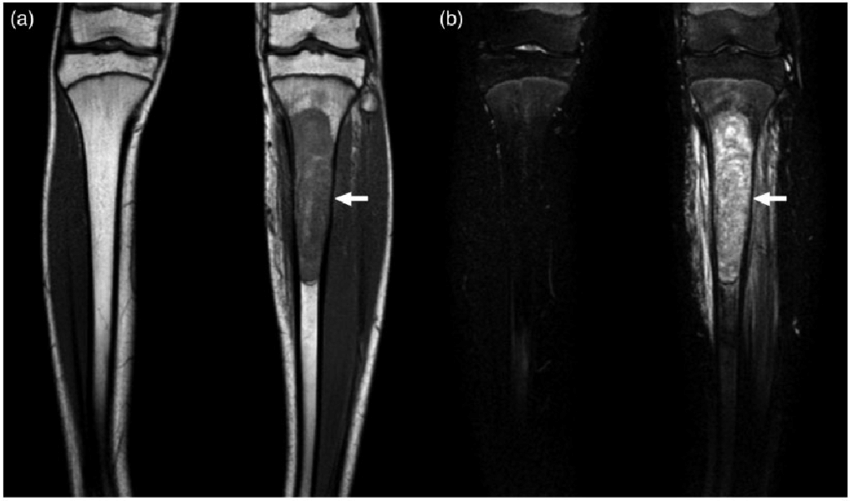

- X-rays and MRI: Evaluate tumor size and bone involvement.

Tibial Sarcoma, also referred to as Osteosarcoma of the Tibia, is a rare but aggressive form of bone cancer that originates in the tibia (shinbone). It typically affects children, adolescents, and young adults during growth spurts but can occur at any age. This malignant tumor originates in the osteoblasts—the bone-forming cells—and often presents with pain, swelling, and reduced mobility.

Tibial sarcoma is classified as a primary bone tumor and requires prompt diagnosis and a multidisciplinary treatment approach involving chemotherapy, surgery, and sometimes radiation therapy. Due to its location, limb-sparing surgical techniques are prioritized whenever possible to maintain function and mobility.